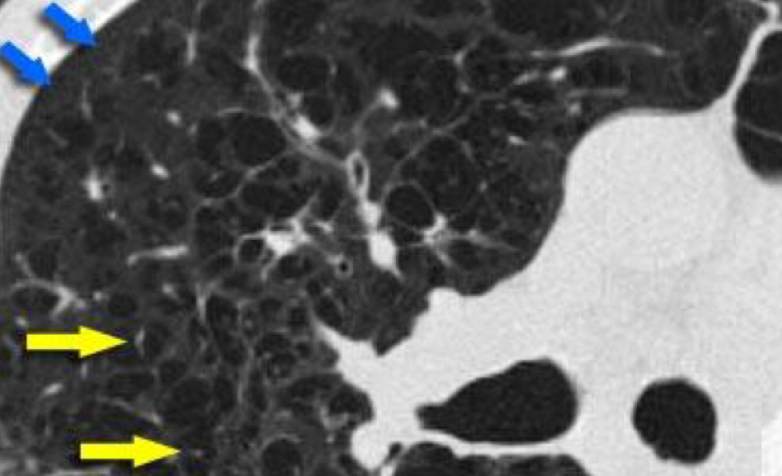

27

Que es y como sabes

bronquitis crónica Señala el sign del manguito peribronquiales->mancha blanca con punto negro